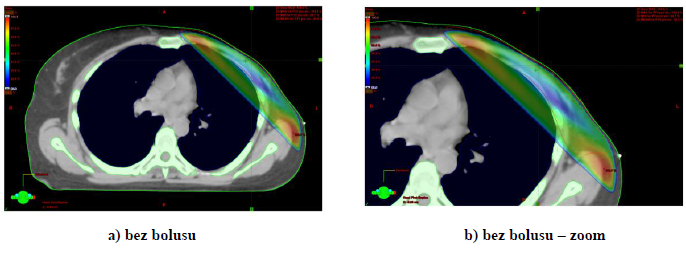

3) Distribuce dávky v oblasti hrudní stěny s bolusem a bez bolusu (TPS Eclipse).

K plánování ozáření s CT skeny používáme simulaci bolusu na hrudní stěně. Tloušťka bolusu ovlivní dávku na povrchu hrudní stěny.

Obr. 1: Distribuce izodoz na hrudní stěně po ablaci pro karcinom prsu